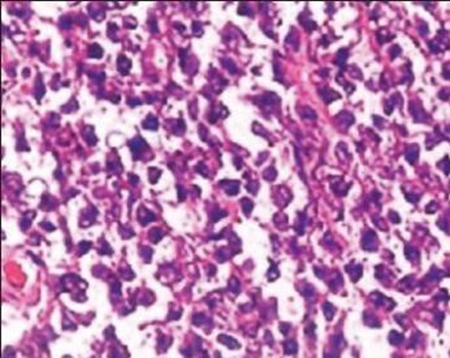

The microscopic examination of the mass reveals that the ovarian tissue is covered by a diffuse carpet of medium-sized cells, with some large cells (Figure 1) in foci, forming cords and trabeculae. The cells have scant cytoplasm, nuclei with aggregated chromatin, and numerous nucleoli (Figure 2). The immunohistochemical examination highlights the presence of cells positive for LCA and negative for cytokeratin, therefore the diagnosis of non-Hodgkin lymphoma with ovarian, omental and peritoneal involvement is made (most likely a diffuse large B-cell lymphoma). The patient undergoes a CT scan for a post-operative check-up which detects multiple lymph node enlargements in the common iliac, internal iliac and external iliac groups. Bone marrow biopsy reveals no marrow infiltrates. The patient is subjected to a chemotherapy protocol which includes 6 cycles of CHOP, but despite the therapy there is progression of the lymphoma with subsequent renal and splenic involvement.

Figure 1: The image shows an ovarian tissue rich in medium volume cells, with large cells in foci, which form cords and trabeculae.

Figure 2: The image shows cells with little cytoplasm, numerous nucleoli and nuclei with aggregated chromatin